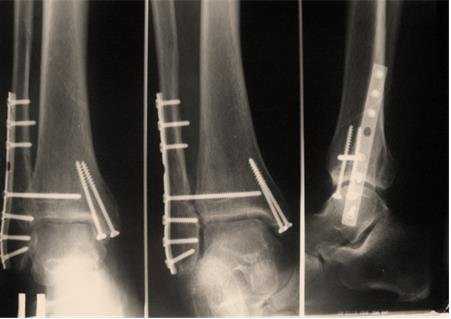

Лечащий врач чаще всего обращается к рентгенологическому исследованию для уточнения локализации и характера травмы, и только после этого ставит окончательный диагноз и назначает вид терапии: консервативную или хирургическую.

С помощью механических приспособлений и титановой арматуры костные отломки стягивают и фиксируют, предварительно прошив разорванные сухожилия, сосуды и мышцы.

Хирургические подходы и методы лечения переломов нижних конечностей разнообразны.